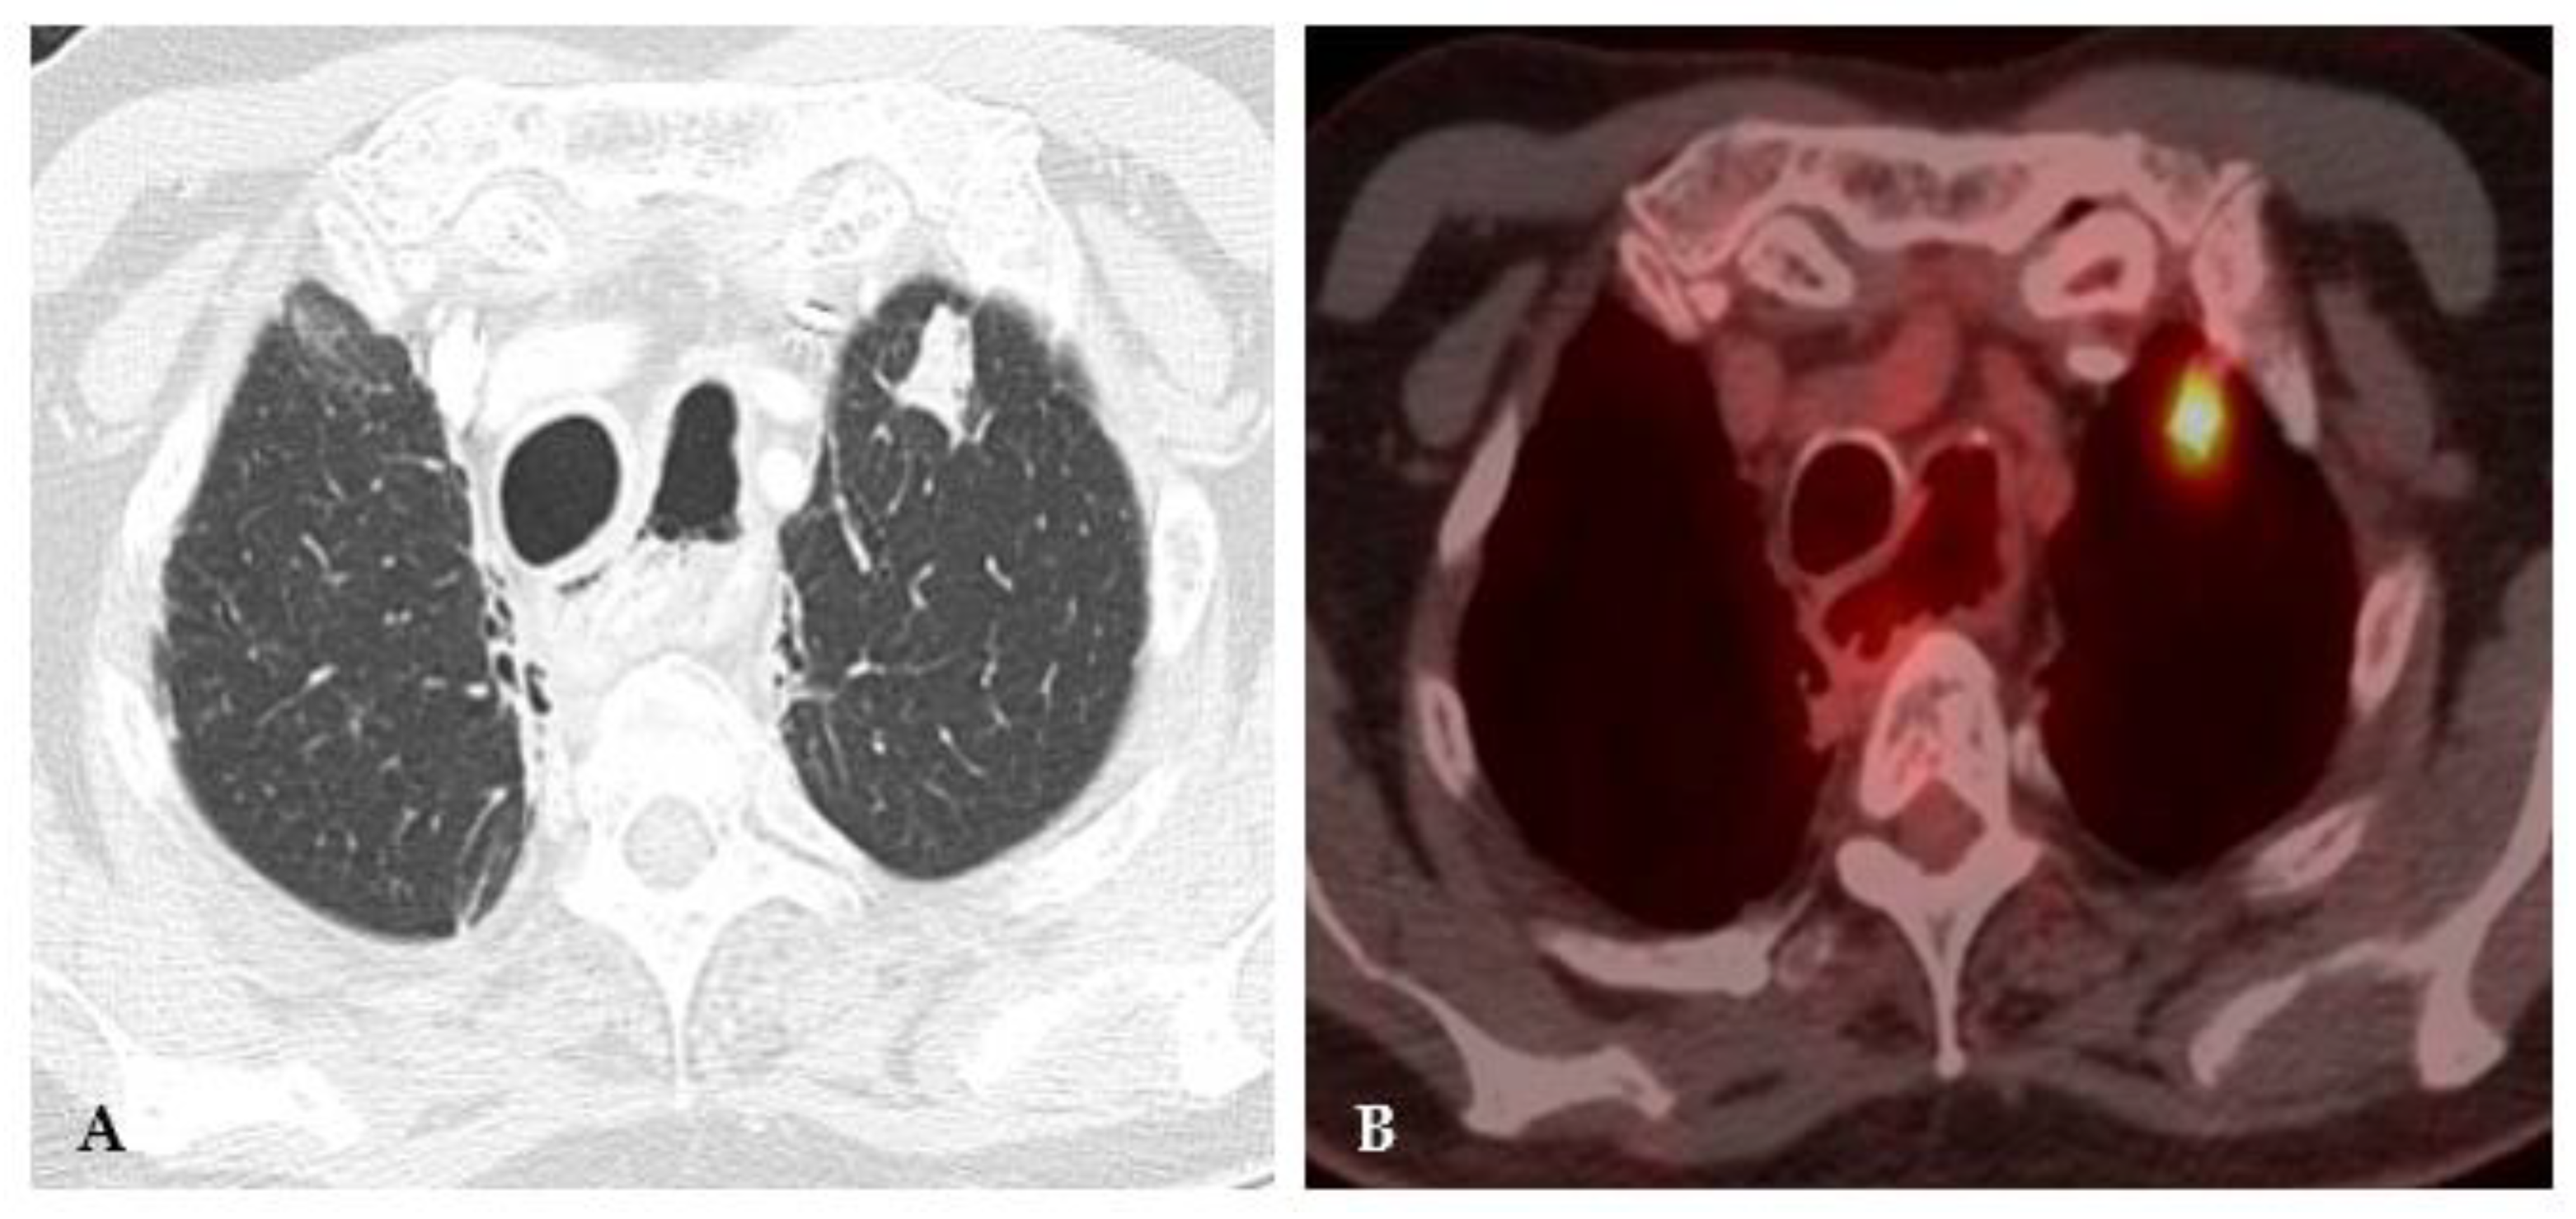

2.4. Disseminated Infection

2.5. Mixed Pattern